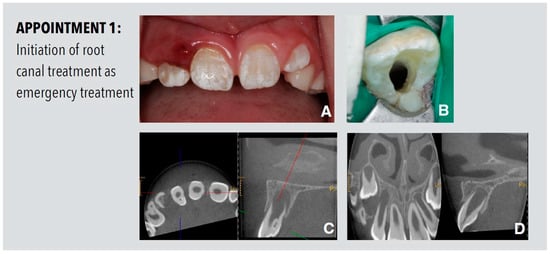

2.1. Appointment 1

A 9-year-old male presented with pain in the anterior region of the upper jaw. The clinical inspection showed a localized swelling and redness of the buccal gingiva of the maxillary right lateral incisor. The tooth had a buccal probing depth of 9 mm and was tender on both apical palpation and percussion. There was no response to a pulp sensibility test with cold. A protuberance with a palatal localized fissure leading to the foramen caecum was detected. Cone beam computed tomography (CBCT) with a limited field-of-view revealed a periapical radiolucency associated with tooth 12, arrested root development and an isolated invagination, which extended up to the cement–enamel junction. A thin bridge of dental hard tissue between the invagination and the true endodontic system could be detected (Figure 1). Thus, the tooth was diagnosed a dens invaginatus of Oehlers Type II with pulp necrosis and apical periodontitis. After informed consent was obtained, the access cavity was prepared and disinfection of the endodontic system started (Figure 1). The root canal was irrigated with 3% sodium hypochlorite, dressed with calcium hydroxide paste (AH Temp, Dentsply Sirona, Konstanz, Germany) and temporized with Cavit W (3M, Seefeld, Germany).

Figure 1.

Procedures performed at the first appointment. (A) Preoperative clinical view of the maxillary front teeth showing swelling and redness of the gingiva in proximity to the right lateral incisor. (B) Initial access cavity. (C) Preoperative diagnostic CBCT shows the palatal invagination with partial enamel lining on tooth 12. (D) The sagittal view of the CBCT shows the periapical radiolucency associated with tooth 12 and arrested root development of tooth 12 in comparison to the unaffected tooth 22. The transversal projection of tooth 22 is shown on the right-hand side.